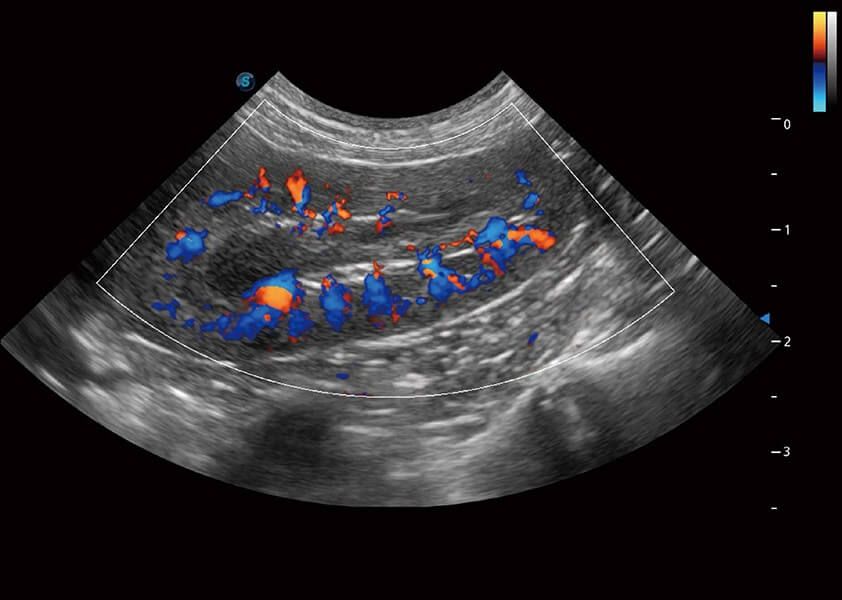

ProPet 60 作为一款高端台式动物超声设备,为动物医生的日常诊断提供了一系列贴合动物临床需求、解决临床实际问题的高级成像功能。凭借全系列高清探头,满足医生对腹部、心脏、生殖、浅表、肌骨等成像的所有需求,切实帮助您提升检查效率,提高诊断信心。

动物是人类最亲密的朋友和最值得信赖的伙伴。银河集团官网也一直致力于探索动物专用的超声影像解决方案。 全新推出的ProPet系列,是银河集团官网在动物超声影像智能化、专业化、精准化的一次跨越式革新。动物不能用言语来表述自己的不适,通过超声影像,ProPet系列搭建了动物医生与不同物种沟通的“桥梁”,为动物医生注入了“治愈之力”。